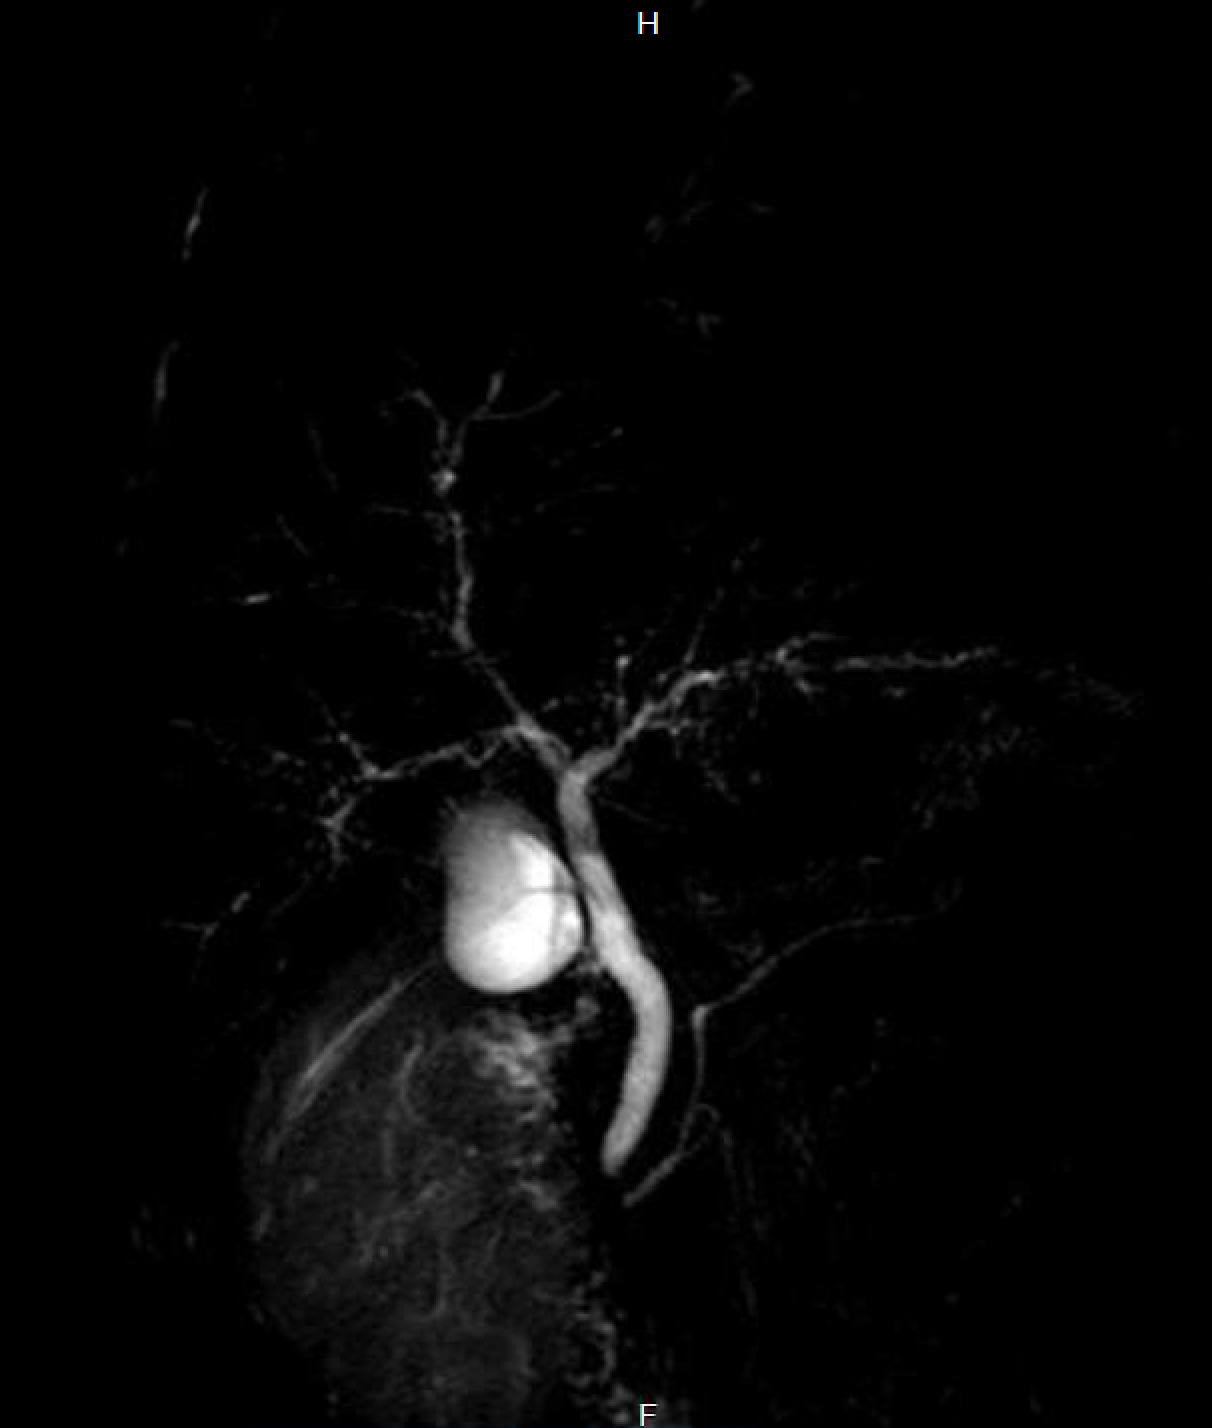

Gallenwegserkrankungen nach COVID-19

In der ersten Version des Long Covid-Themas hatte ich ja schon die beiden mir bekannten Hamburger Fälle einer sekundär sklerosierenden Cholangitis nach COVID-19-Erkrankung beschrieben, einmal aus unserem Krankenhaus und einmal aus der Asklepios Klinik Altona (mit Veröffentlichung im Hamburger Ärzteblatt, S. 32-33, Link, Link Wikipedia), nach einer schwer verlaufenden COVID-Pneumonie bei einem 19-jährigen Patienten. In unserer Klinik wurde die selbe Diagnose bei einem 51-jährigen Patienten mit ebenfalls schwerst verlaufender COVID-Pneumonie und sekundärer Pilzpneumonie gestellt, den wir nach einer intensivmedizinischen dreimonatigen Beatmungstherapie (11/2020-01/2021) von unserer Intensivstation in die Frührehabilitation übernommen hatten.

Die sekundär sklerosierende Cholangitis ist sicherlich keine COVID-spezifische Erkrankung, sondern kommt auch nach anderen schwersten intensivmedizinisch zu versorgenden Erkrankungen vor, ist aber auch so selten, dass zwei Fälle in Hamburger Kliniken in kurzer Zeit sicherlich erwähnenswert sind. Und natürlich kann man in jedem Fall argumentieren, dass beide Patienten diese (häufig zur Notwendigkeit einer Lebertransplantation führende) Erkrankung nicht entwickelt hätten, wenn sie keine COVID-Infektion erlitten hätten. Mittlerweile findet man auch Literatur und andere Fallberichtsserien zu dem Thema (z.B. Durazo et al.).